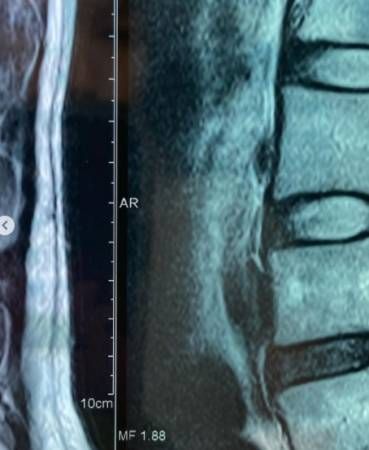

雅慧背部受伤。